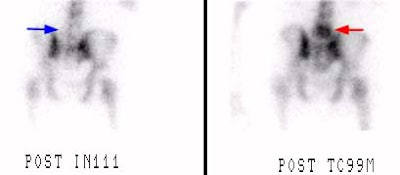

L5 vertebral osteomyelitis: The case below also illustrates the decreased sensitivity of In-111 WBC imaging for the detection of vertebral osteomyelitis. Bone scan revealed increased tracer activity within L5 (red arrow) in a patient with osteomyelitis at this level. The In-111 WBC exam demonstrated no evidence of increased tracer accumulation in L5 (blue arrow). Case submitted by Dr. Marc Cote, D.O. |